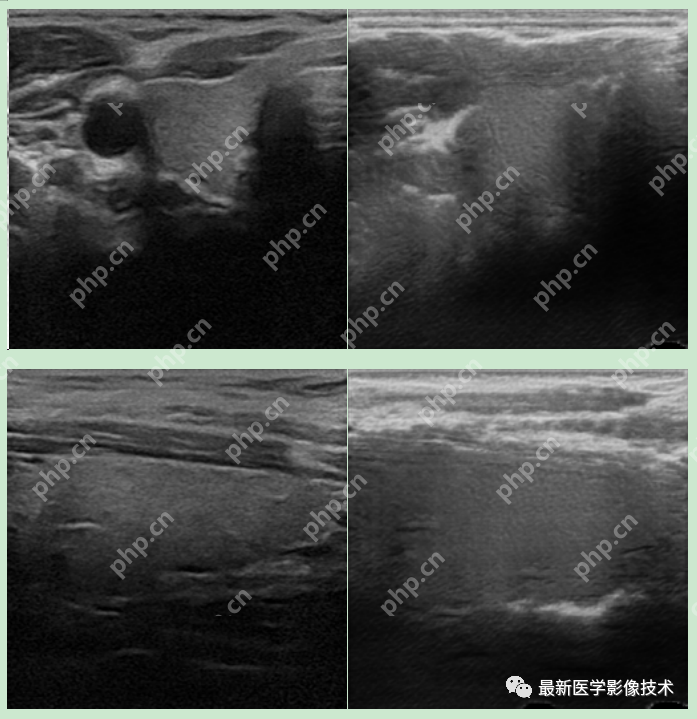

6、测试集部分生成结果

左图为低质量图像,右图为生成的高质量图像。